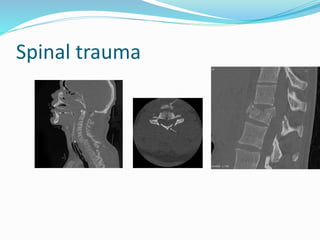

Spinal trauma